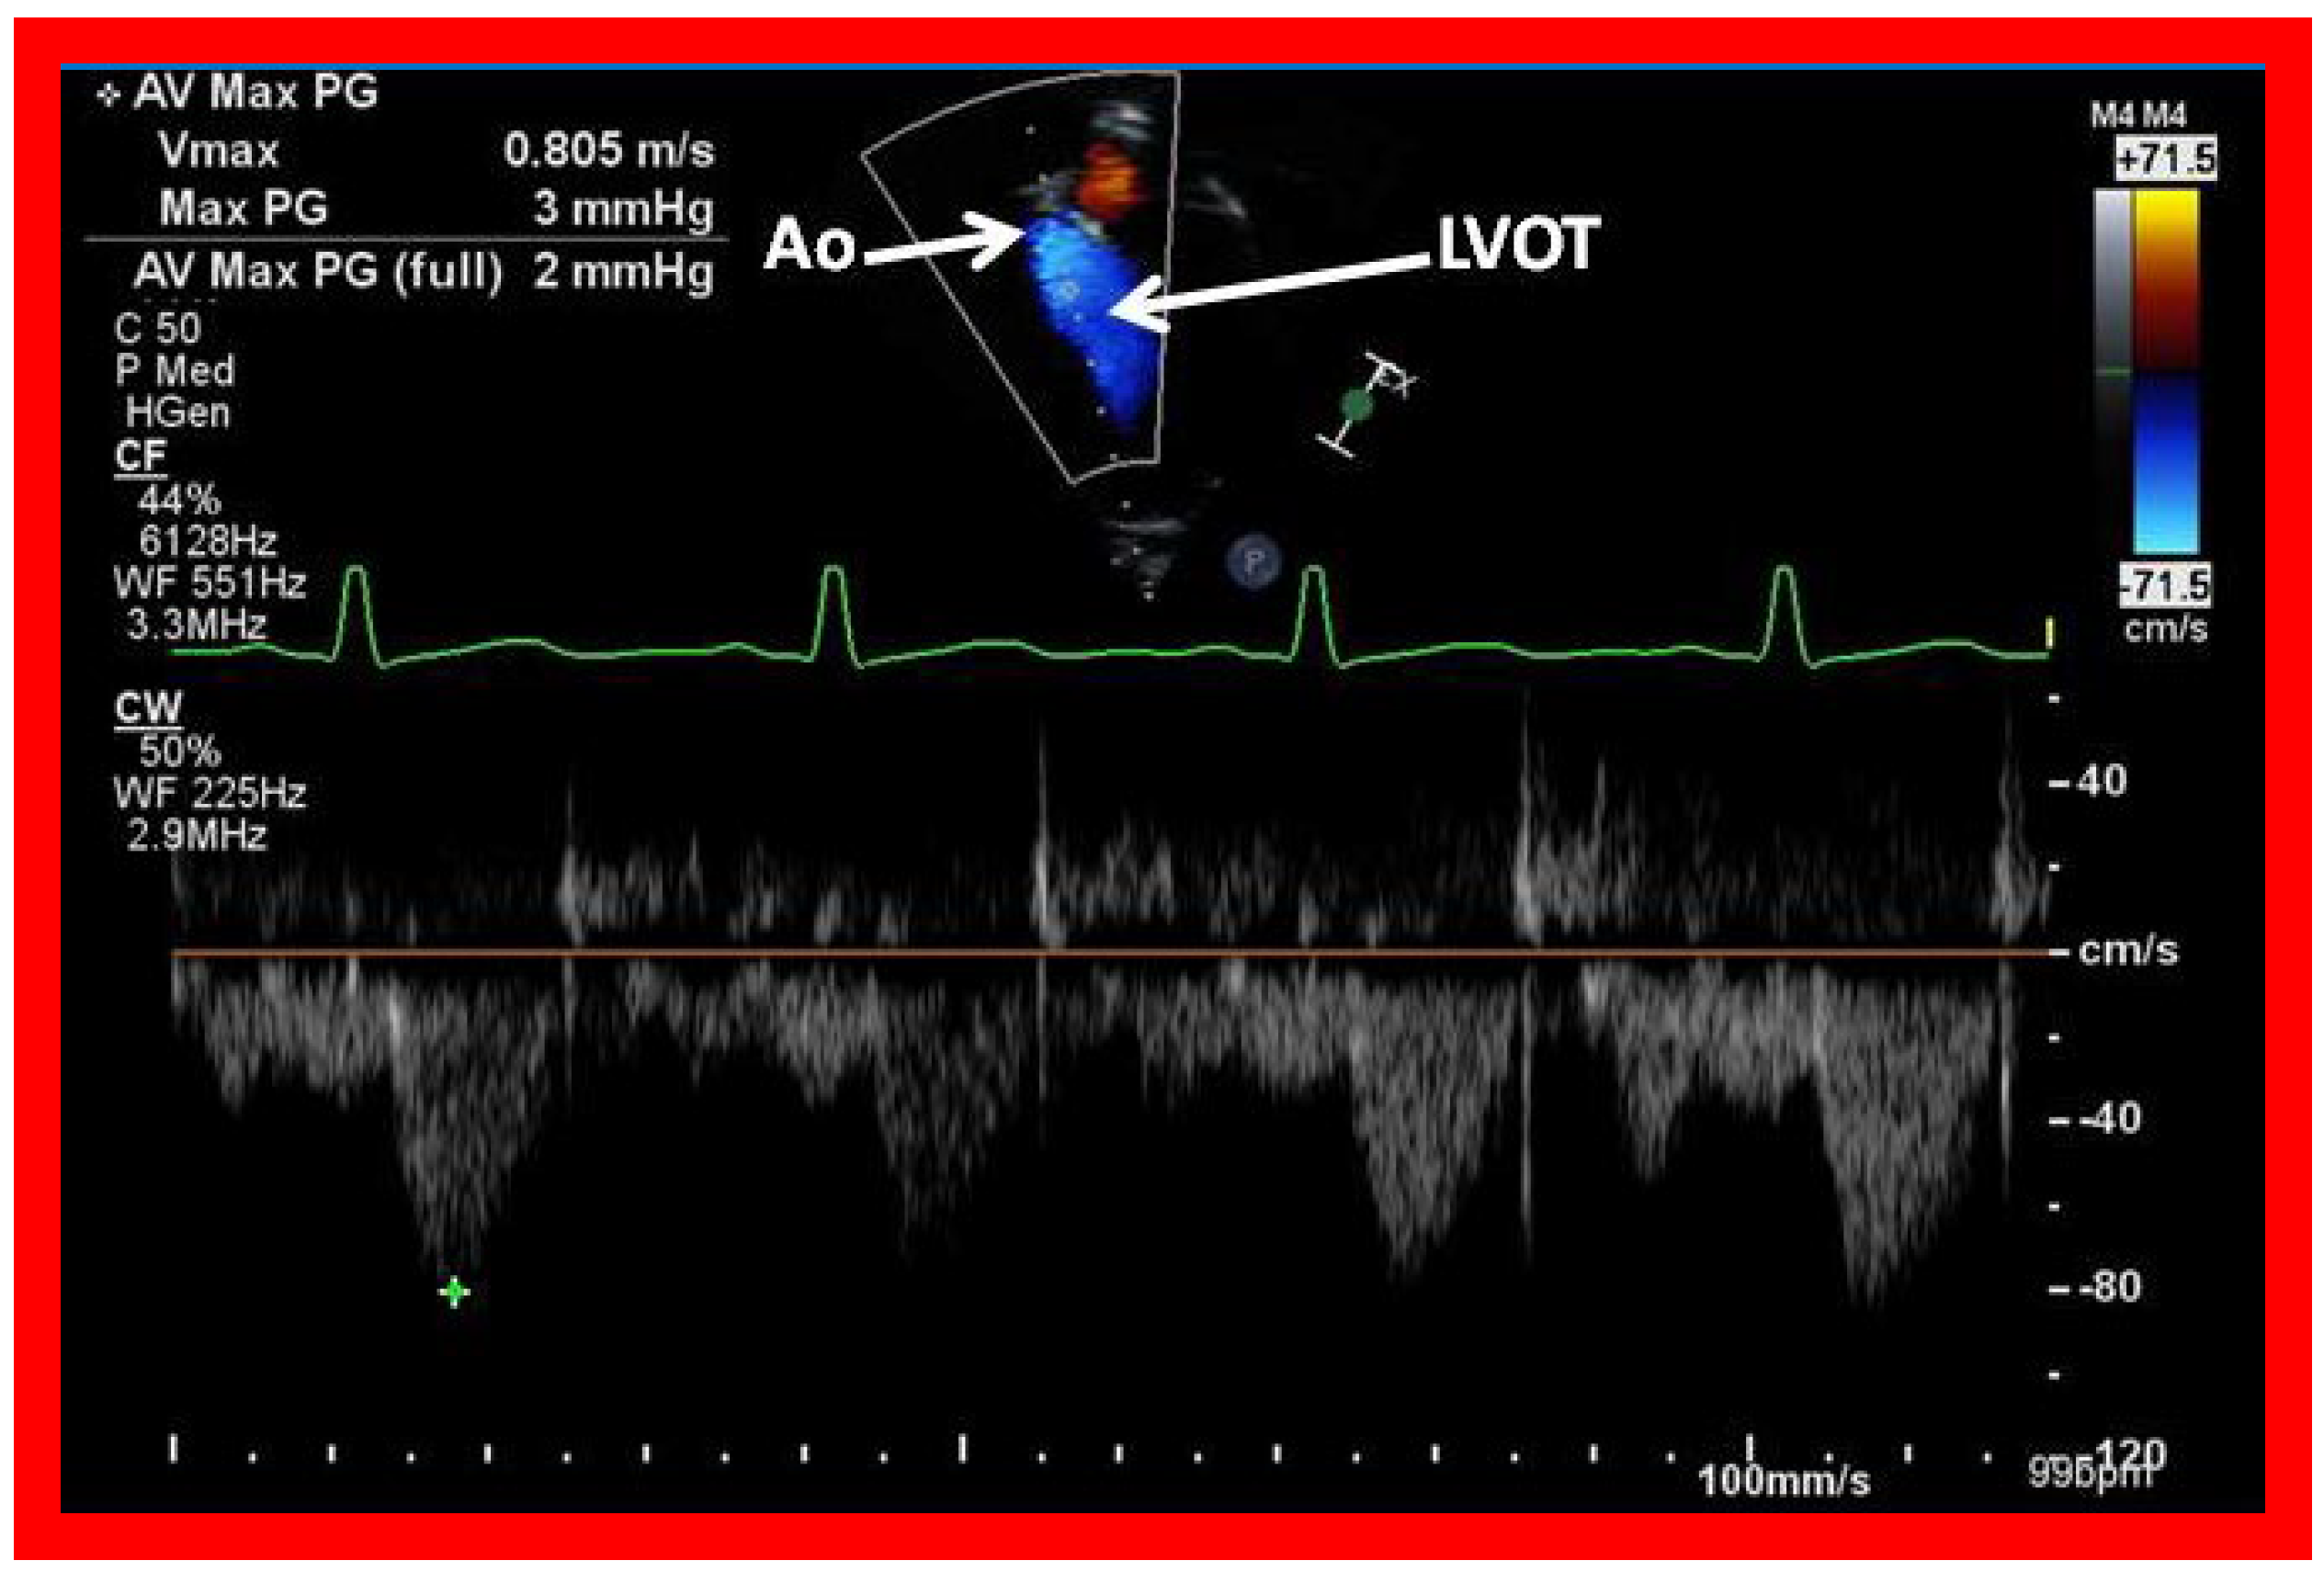

Figure 42. Selected video frames from an apical view demonstrating laminar flow from the left ventricle into the aorta (Ao). Note laminar flow in the LV outflow tract (LVOT) and low Doppler flow velocity (~0.8 m/s).

The LA is usually normal in size (Figure 38, Figure 39 and Figure 40) and empties into the LV; laminar flow across the mitral valve (Figure 41A) can be seen. Drainage of all four pulmonary veins into the LA may be demonstrated by color flow mapping in multiple echocardiographic views. The LV is either normal in size or slightly dilated. In type I patients with normally related great arteries, the LV outflow into the aorta is demonstrable on echo-Doppler with laminar, unobstructed flow with near normal (~1.0 m/s) Doppler flow velocity (Figure 41B and Figure 42). The RV is small and hypoplastic (Figure 39 and Figure 40). If the VSD has already spontaneously closed (Figure 40), the RV has no communication with any other structures since the connection with the PAs has been severed during bidirectional Glenn or Fontan procedures. If the VSD did not undergo spontaneous closure, the RV forms a cul-de-sac connection with the LV (Figure 39 and Figure 43). In Type I patients with atresia of both tricuspid and pulmonary valves (Type Ia), the hypertrophied RV may protrude into the LV outflow region (Figure 44). However, there is usually no evidence for obstruction across this region (Figure 45).